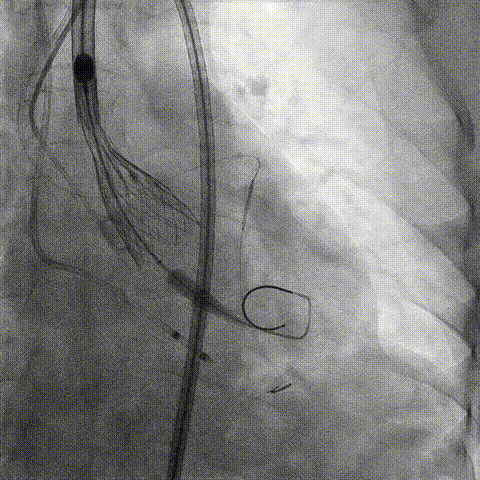

预置Telescope™导引延长导管及导丝保护左冠,

18mm球囊预扩张再次评估冠脉闭塞风险。

介入经过及结果

Telescope™+Runthrough

18mm*40mm 预扩张

预埋 Resolute Integrity 3.5*26mm

再次评估左冠开口